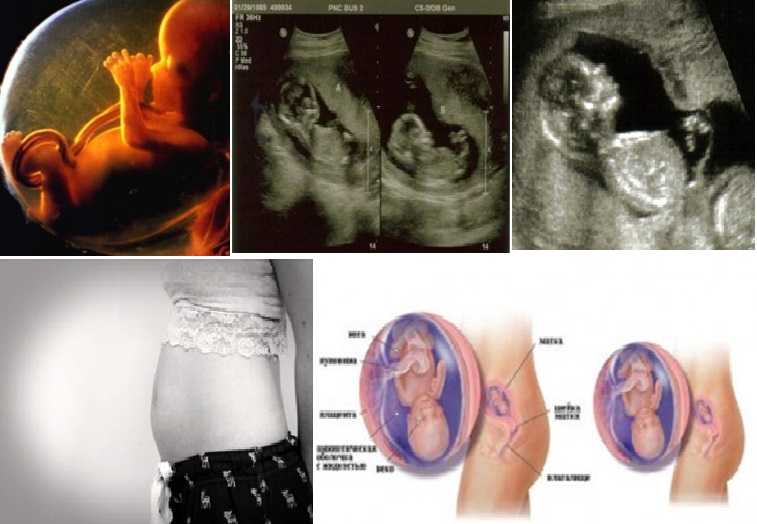

Фотография Плода В Животе

Фотография Плода В Животе 113 фотографий